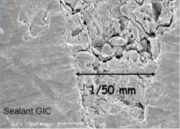

| 09:41, 18 ביוני 2013 | איטומי חריצים7.png (קובץ) |  |

66 קילו־בייטים | Motyk | 1 | |

| 09:33, 18 ביוני 2013 | איטומי חריצים6.png (קובץ) |  |

47 קילו־בייטים | Motyk | 1 | |